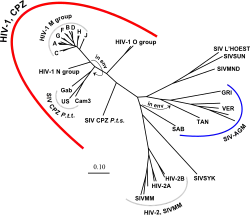

O vírus da imunodeficiência símia (VIS) evoluiu para diversas estirpes, classificadas em função da espécie do hospedeiro natural. Pensa-se que as estirpes de VIS dos géneros Chlorocebus (VISagm) e Cercocebus atys (VISsmm) tenham tido uma longa história evolutiva em paralelo com os seus hospedeiros. Estes hospedeiros adaptaram-se à presença do vírus,[70] que está presente em grande quantidade no seu sangue mas espoleta apenas uma resposta imune moderada,[71] não provoca o aparecimento da SIDA símia,[72] e nem sofre as amplas mutações e recombinações típicas da infeção do VIH em seres humanos.[73]

Em contraste, quando estas estirpes infetam espécies que não estão adaptadas ao VIS, os animais desenvolvem SIDA e o vírus gera diversidade genética semelhante à que é observada na infeção humana com o VIH..[74] O SIV em chimpanzés (VIScpz), o parente genético mais próximo do VIH-1, está associado a maior mortalidade e sintomas semelhantes à SIDA no seu hospedeiro natural.[75] O VIScpz aparenta ter sido transmitido aos chimpanzés e à população humana há relativamente pouco tempo, pelo que os seus hospedeiros não estão ainda adaptados ao vírus.[70] Este vírus também perdeu a função do gene Nef que está presente na maior parte dos VIS; sem esta função, é mais provável que ocorra a diminuição dos linfócitos T, levando à imunodeficiência.[75]

Foram identificados três grupos de VIH-1 com base nas diferenças entre a região do envelope (env): M, N e O.[76] O grupo M é o mais prevalente e é subdividido em oito subtipos (ou clados) com base no genoma completo, que são distintos em termos geográficos.[77] Os mais prevalentes são os subtipos B (encontrados principalmente na Europa e América do Norte), A e D (encontrados principalmente em África), e C (encontrado principalmente em África e na Ásia). Estes subtipos formam ramos na árvore filogénica que representam a linhagem do grupo M do VIH-1. A co-infeção com diferentes subtipos suscita formas recombinantes circulantes (FRC ou, em inglês, CRF). Em 2000, o último ano em que foi feita uma análise da prevalência à escala global dos subtipos, 47,2% das infeções eram do subtipo C, 26,7% eram do subtipo A/CRF02_AG, 12,3% eram do subtipo B, 5,3% do subtipo D, 3,2% eram CRF_AE, e os restantes 5,3% eram constituídos por outros subtipos e formas recombinantes.[78] Grande parte da investigação relativa ao VIH-1 está focada no subtipo B e poucos laboratórios se focam nos restantes subtipos.[79] Tem sido colocada a hipótese de um outro grupo "P", com base num vírus isolado em 2009. A estirpe aparenta ser derivada do VIS do gorila (VISgor), isolada pela primeira vez em 2006.[80]